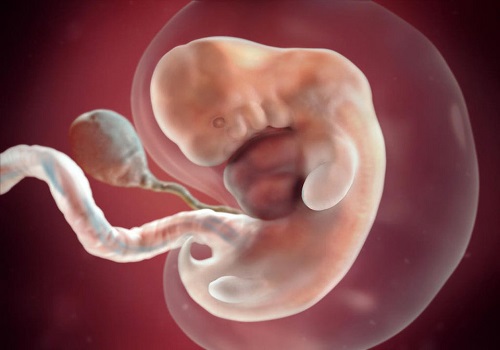

Phá thai 7 tuần hết bao nhiêu tiền? Các yếu tố quyết định đến chi phí

Phá thai 5 tuần tuổi có được không? Phương pháp an toàn

Phá thai 1 tuần có thực hiện được không? Lưu ý những gì

Những điều cần biết về cách phá thai 2 tuần tuổi an toàn

Phá thai 3 tháng tuổi có an toàn không? Lưu ý những gì

Phá thai 2 tháng tuổi có nguy hiểm không?

Tìm hiểu phương pháp phá thai 1 tháng an toàn và không đau

Đình chỉ thai bằng thuốc thực hiện cho tuổi thai nào? Ở đâu an toàn